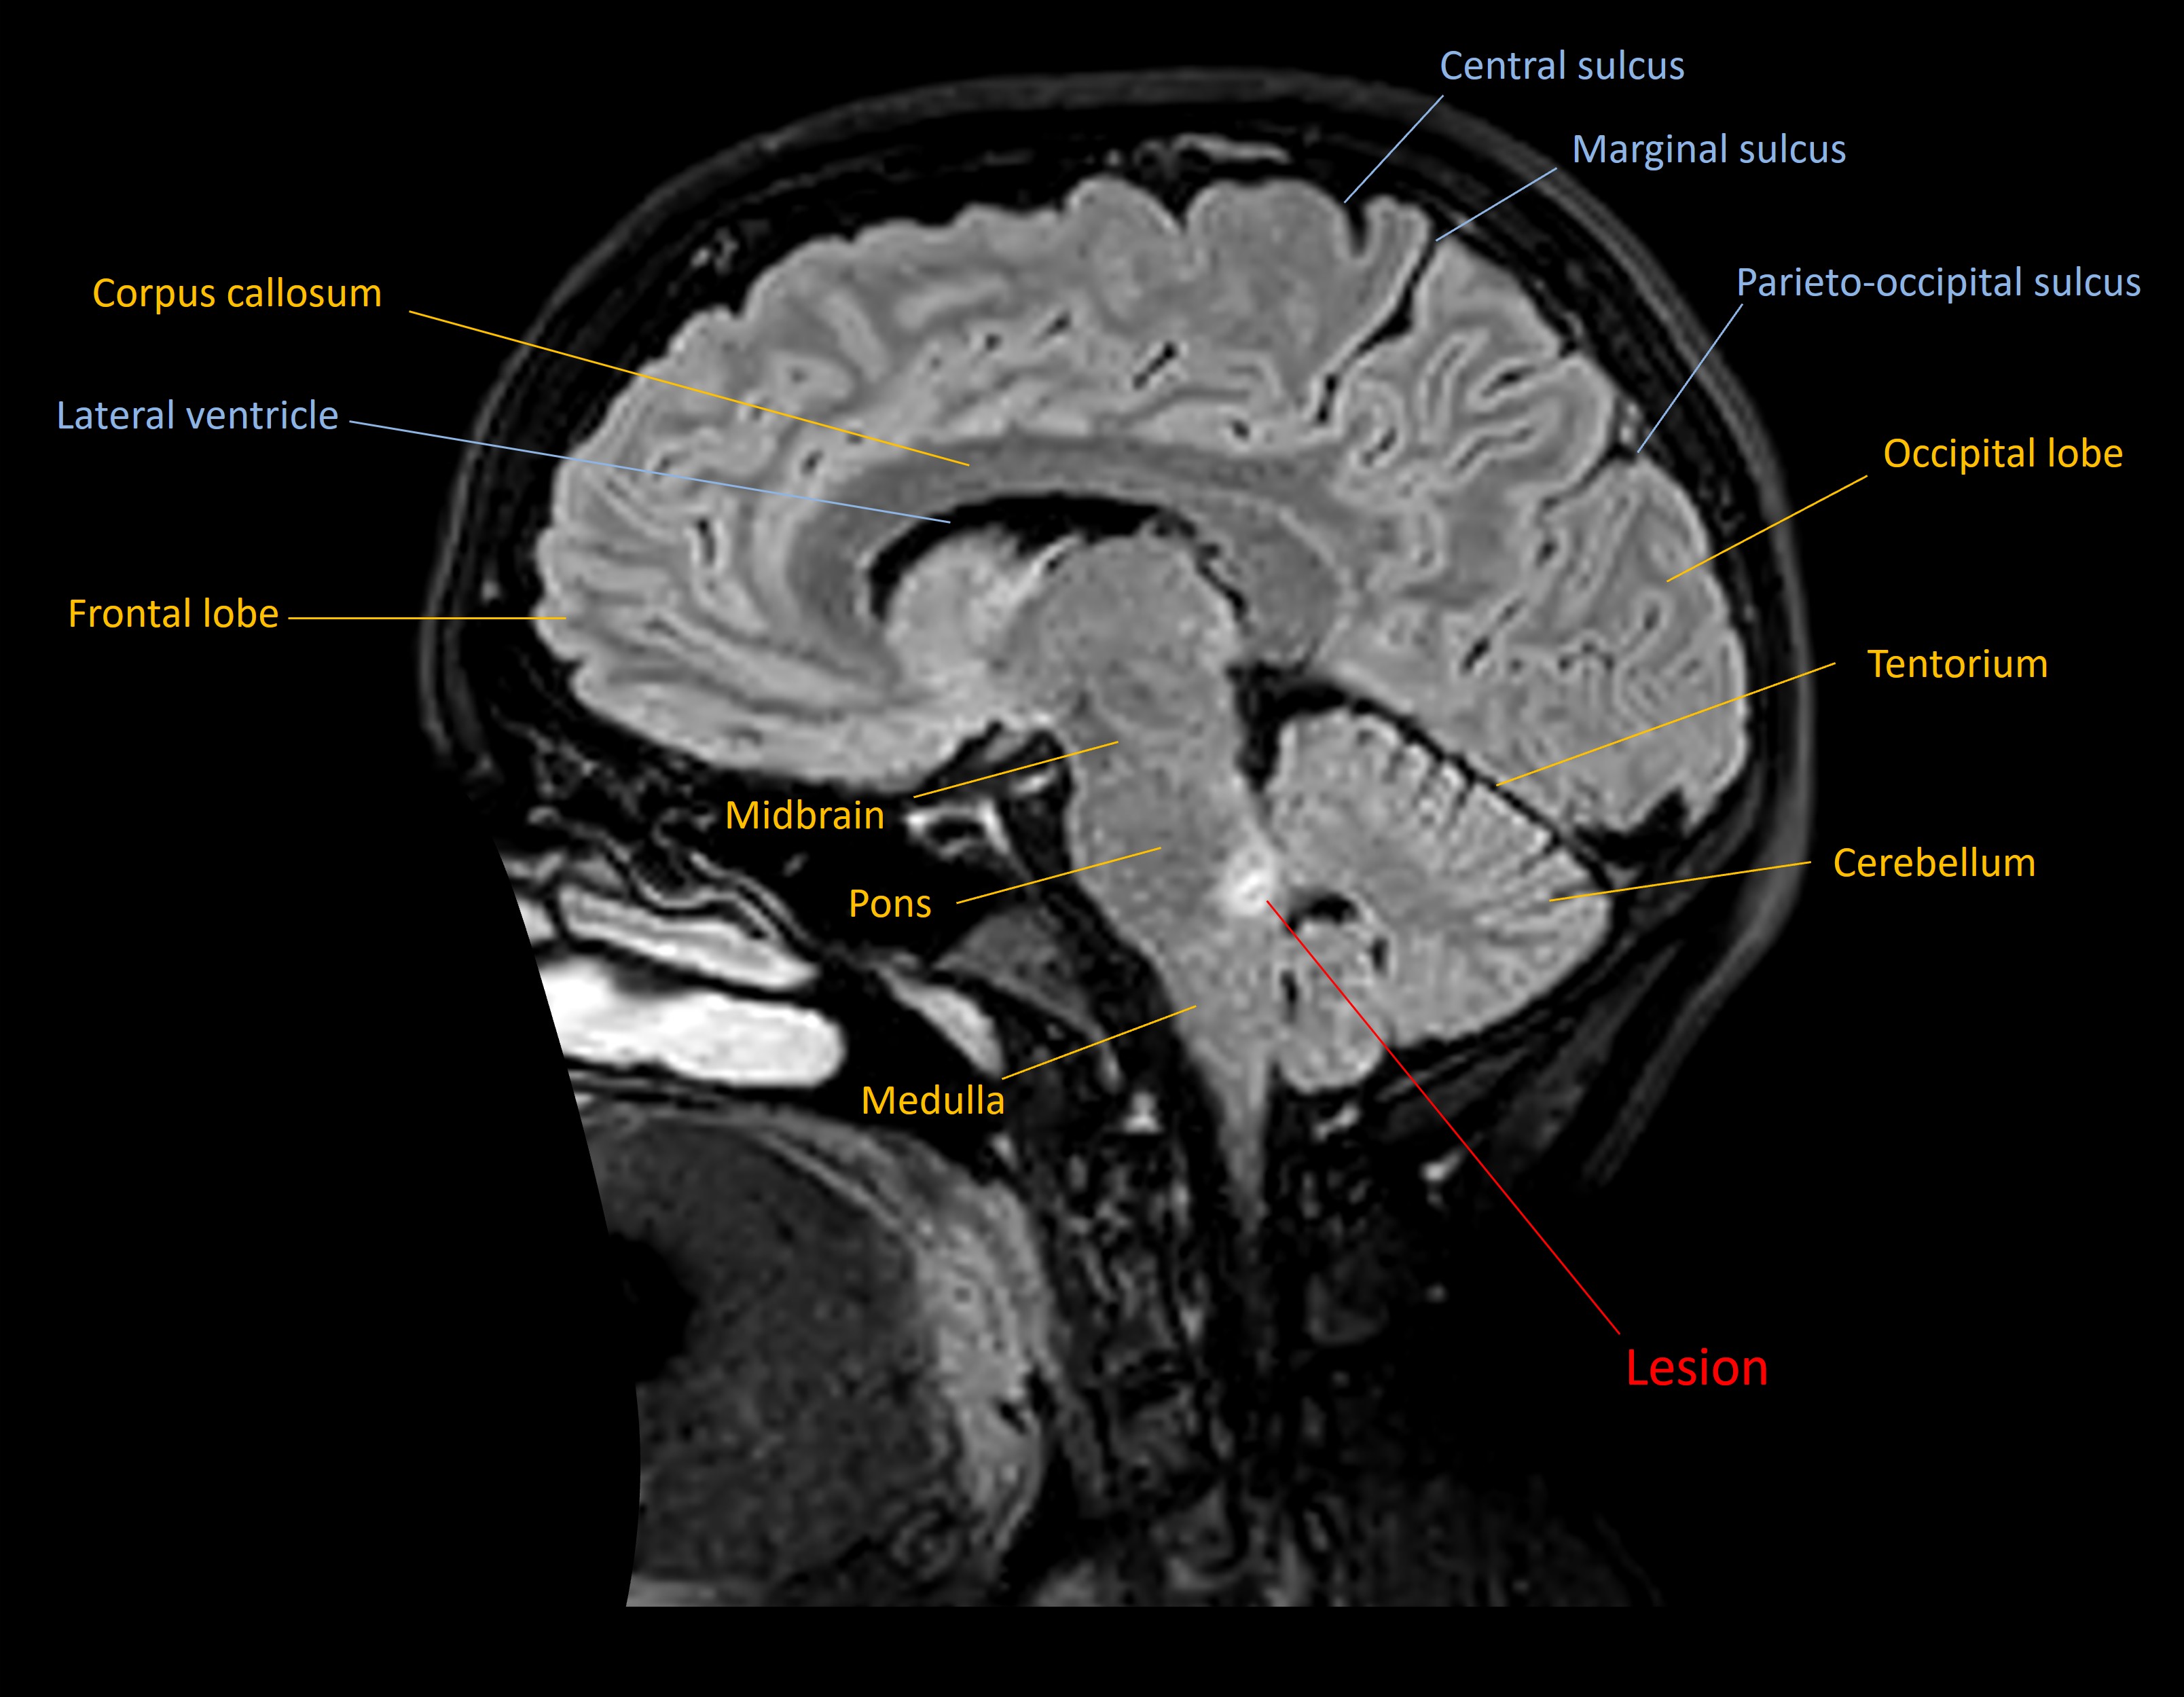

An MRI showed a lesion in the left dorsal upper pons, in the site of the principal trigeminal sensory nucleus - suggestive of demyelination.

Hemifacial numbness due to a demyelinating pontine lesion as the first presentation of MS.